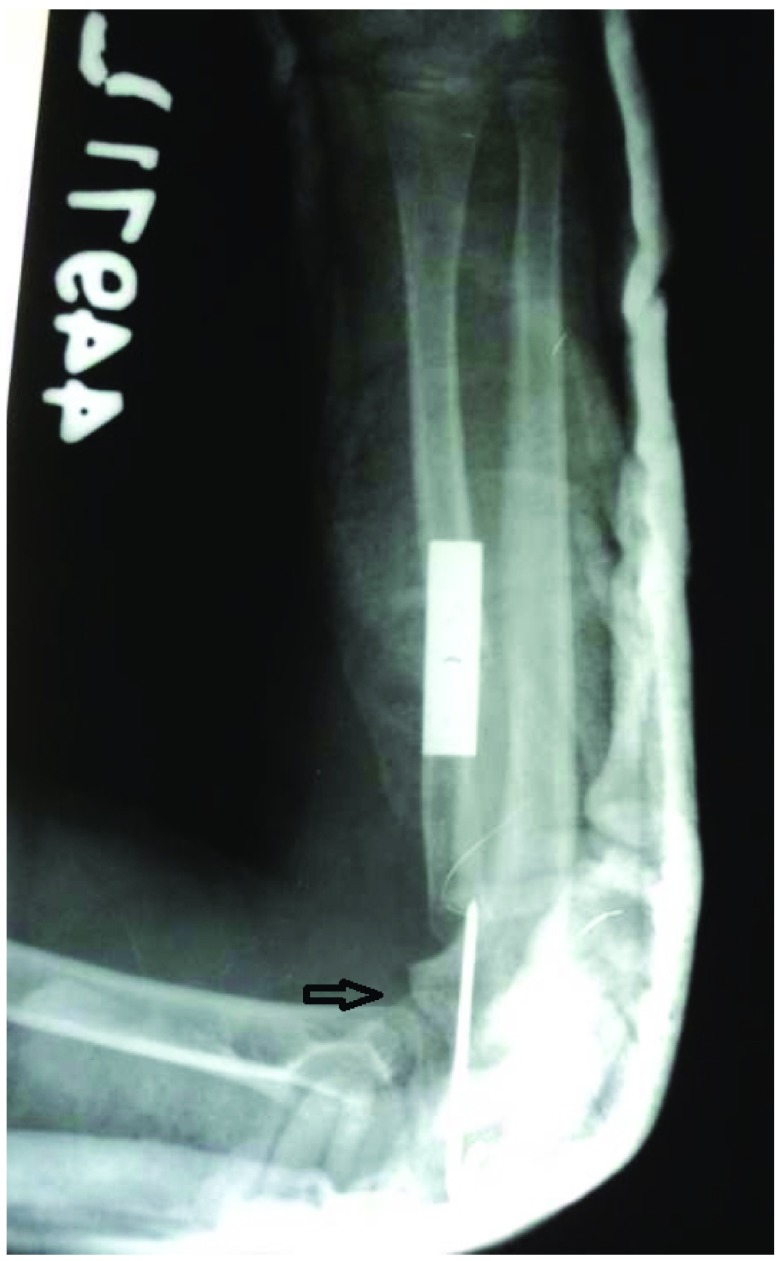

Figure 2. Immediate post-operative X-ray with radial shortening and fixation with plate and screws.

The radial bow is corrected. The radial head is fixed with a transarticular pin.

An X-ray showed posterior dislocation of the radial head with a domed articular surface. McLaughlin’s line had not bisected the capitellum. The radius was bowed anteriorly and was relatively longer in relation to ulna. The capitulum was hypoplastic and flat. There was no evidence of any previous fracture ( Figure 1). An MRI showed posterior dislocation of the radial head and formation of a pseudo-joint with the adjacent margin of the ulna ( Figure 2). Due to relative radial lengthening and radial bow, it would have been difficult to reduce the radial head in the radiocapitellar joint. Hence we planned for reconstruction surgery by radial shortening and open reduction of the radiocapitellar joint through two incisions. Pre-operative templating was done to assess the amount of shortening required for the easy reduction and maintenance of adequate joint space.

At one year follow up in 2013, the patient’s elbow was stable with no valgus or fixed flexion deformity. Supination had increased to 40 degrees from zero degrees. An X-ray showed reforming of the radial head articular surface with good congruity of the radiocapitellar joint with no deformity of the radial shaft ( Figure 3).